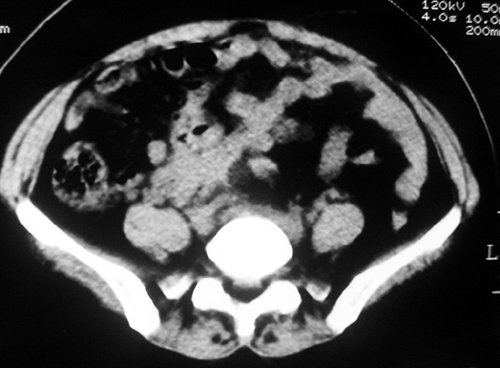

以下是引用余辉在2009-2-14 8:37:00的发言:[br]宫颈左后壁见较大低密度肿物影且向左后上方突出,宫腔内见大片状低密度区,考虑宫颈肿瘤,宫颈癌可能性大,伴宫腔积液或转移